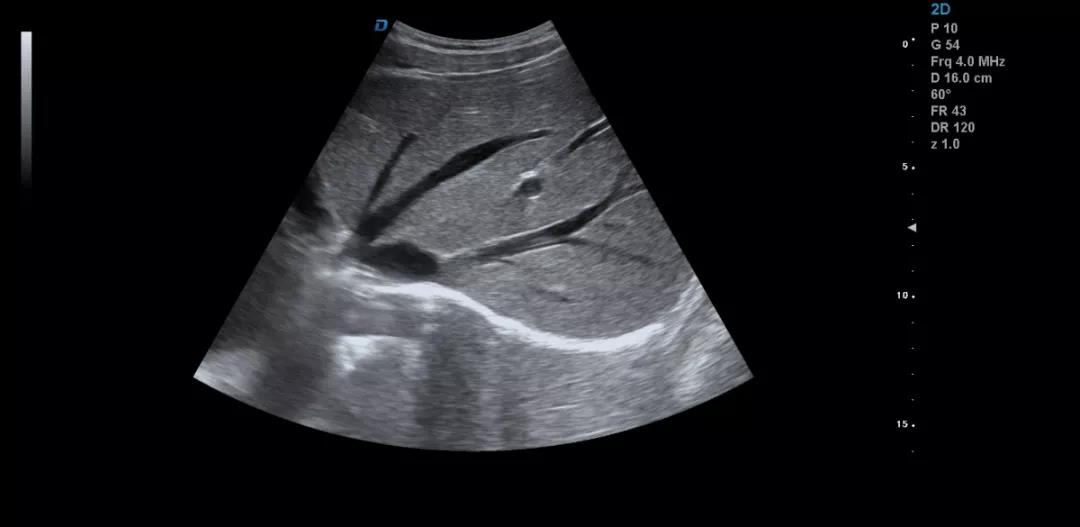

彩超機(jī)肝臟超聲的檢查方法詳解

彩超機(jī)是每個(gè)醫(yī)院常見(jiàn)的診斷設(shè)備,很多人都不陌生。可能大家認(rèn)為彩超機(jī)檢查醫(yī)生很輕松,其實(shí)不然,彩超檢查醫(yī)生也是需要精湛的操作技術(shù),專業(yè)的判斷才可以的。下面小編和大家一起來(lái)看下利用彩超機(jī)檢查肝臟超聲的方法。

彩超機(jī)檢查肝臟超聲方法

彩超檢查不同于其他的影像學(xué)檢查方法,彩超檢查的結(jié)果與操作者的技術(shù)、經(jīng)驗(yàn)、手法、檢查細(xì)致程度等很多因素密切相關(guān)。

眾所周知,肝臟有很多檢查死角,成為超聲檢查的盲區(qū),如肺和骨所掩蓋處,肝右前上段及右后上段的膈頂部,左外葉外側(cè)角區(qū),沿肝臟表面的肋骨下區(qū)等等部位,只有極其細(xì)致的檢查配上精巧的手法才能盡可能的顯示清楚這些部位。

如果我們能夠細(xì)致的檢查每個(gè)病人,所謂的肝臟死角能夠盡可能的探測(cè)到,肝臟的死角其實(shí)只有膈頂部,其他的部位如果能細(xì)致檢查都可以探測(cè)到。

肝左葉掃查時(shí),矚患者深吸氣,可以盡量使肝下移,更接近體表,顯示清楚,掃查至外側(cè)角肝臟消失的位置。然后探頭連續(xù)滑動(dòng),沿肋緣下斜切,矚患者深吸氣,探頭做扇形掃查,盡可能側(cè)動(dòng)探頭至與皮膚平行,肝臟的絕大部分病變不會(huì)被遺漏。

對(duì)于肥胖體型或腹腔臟器明顯的,這種方法就不合適,可以采取肋間斜切的方法,自下而上逐個(gè)肋間連續(xù)掃查,注意不要做跳躍式掃查,這樣容易眼花也容易遺漏病變。

肝臟膈頂部掃查體會(huì):

1)一般是讓患者深吸氣,讓肝臟下移,然后探頭盡量上翹;

2)當(dāng)然很多患者因肥胖或肺氣的干擾會(huì)顯示更差,這時(shí)我就讓患者深呼氣,把氣全部吐干凈,然后屏氣掃查;

3)還有就是不要沿著肋間隙掃查,而是和肋間隙成一定的角度緩慢向右上方腋前線掃查;

4)在平臥位掃查時(shí),在橫切腎臟時(shí)探頭盡量上翹,甚至與腹壁平行,當(dāng)然在右側(cè)肋緣下也行;

5)變換體位掃查,肝臟因重力作用產(chǎn)生移位。左側(cè)臥位、右側(cè)臥位、各種斜位、還有站立位等等。

掃查肝臟時(shí)要配合患者的呼吸運(yùn)動(dòng),采取你動(dòng)我靜,你靜我動(dòng)的掃查方法,并最大限度的側(cè)動(dòng)探頭,最大角度的顯示肝臟。

發(fā)現(xiàn)肝臟病變時(shí)要多切面多角度掃查,可以了解病變的解剖位置并排除假陽(yáng)性。